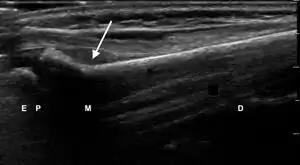

| Sonographic Features of Pediatric Distal Forearm Bones | # | Fracture Subtype | Fracture Description | Sonographic Signs | Ultrasound Image |

| 1 | No Fracture | "Unbroken" |

|

![]() | |